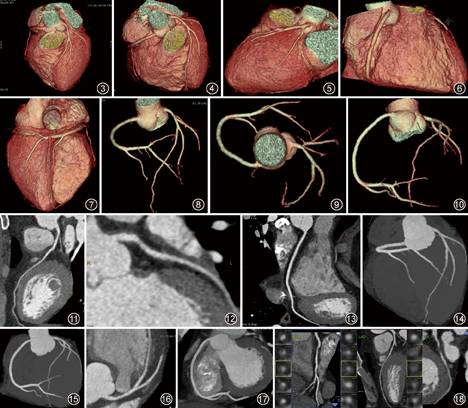

CCTA三维重建和摄片体位推荐参照CAG投照角度,但是CCTA图像不同于CAG,以能最清晰显示病变的最佳角度为准,摄片序列如下(图3-18)。建议按左主干、前降支(包括较粗大的对角支)、回旋支(包括较粗大的钝缘支)和右冠状动脉(包括较粗大的后降支和左室后支)顺序进行三维重建和摄片,并作出文字标记。推荐摄片的窗宽设置为600~900 HU,窗位设置为250~350 HU。对于CT对比度高、钙化多或有支架的患者,窗宽适当放宽,窗位适当提高。因横断面图像过多,建议仅对上述三维重组图像和有意义的垂直截面图像进行摄片(2~4张胶片),推荐对所有横断和三维图像刻入光盘(标准DICOM 3.0图像),并给予患者,以便存储、会诊,减少不必要的重复检查。有PACS系统的单位,采用标准图像格式存储于PACS系统中。

图3~7 容积再现(VR)图像。图3主要观察左主干、前降支和对角支,采用左前斜位60° 足头位60°(LAO 60° CRA 60°)。图4主要观察左主干、前降支和右冠状动脉近段,采用左前斜位0° 足头位60°(LAO 0° CRA 60°)。图5主要观察前降支近中段和和回旋支,采用左前斜位130° 足头位30°(LAO 130° CRA 30°)。图6主要观察右冠状动脉近中段,采用右前斜位30° 足头位0°(RAO 30° CRA 0°)。图7主要观察右冠状动脉远段和后降支、左室后支,采用右前斜位120° 头足位60°(LAO 120° CAU 60°)

图8~10 仅保留冠状动脉的VR血管树图像。图8可以同时观察左、右冠状动脉及其部分分支血管,采用左前斜位30° 足头位40°(LAO 30° CRA 40°)。图9类似CAG的”蜘蛛位” ,可以同时观察左右冠状动脉及其部分分支血管,利于观察左主干、前降支和回旋支分叉,以及右冠状动脉开口和近段,采用左前斜位120° 足头位70°(LAO 120° CRA 70°)。图10主要观察左前降支的中远段、右冠状动脉全程,采用左前斜位30° 头足位10°(LAO 30° CAU 10°)

图11~13 曲面重组(CPR)图像。图11为沿左冠状动脉开口至前降支末梢的中心线所做的CPR图像,主要观察左主干和前降支的全程,利于显示管腔狭窄和斑块的关系。图12为沿左冠状动脉开口至回旋支(或粗大钝缘支)末梢的中心线所做的CPR图像,主要观察左主干和回旋支的管腔情况。图13为沿右冠状动脉开口至后降支或左室后支末梢的中心线所做的CPR图像,主要观察右冠状动脉的全程

图14~17 最大密度投影(MIP)图像。图14为仅保留冠状动脉的MIP图像,该序列图像利于显示钙化斑块的存在,但钙化斑块容易遮挡管腔,利于观察非钙化斑块导致的管腔狭窄。本图主要用于观察左前降支的中远段和对角支、右冠状动脉近段和远段(包括后降支),采用左前斜位10° 足头位60°(LAO 10° CRA 60°)。图15为仅保留冠状动脉的MIP图像,主要用于观察右前降支全程和后降支、左室后支,采用左前斜位30° 头足位0°(LAO 30° CAU 0°)。图16采用薄层(10 mm)MIP技术,主要用于显示左主干和左前降支的近中段,以及对角支。图17采用薄层(10 mm)MIP技术,主要用于显示右冠状动脉

图18 血管轴面图像(cross-sectional images)。对于有病变的冠状动脉血管,CPR图像用于展示血管腔及其狭窄所在的斑块,斑块局部采用垂直长轴的横断面图像,利于显示斑块与管腔和管壁的关系,甚至对斑块导致的”血管重构” ,以及依据斑块内部强化是否均匀等情况判定”餐巾环征” (一种易损斑块的CT征象)十分必要。从左至右,依次显示右冠状动脉(RCA)、前降支(LAD)和回旋支(CX)的血管狭窄和斑块及其横断面图像(多个小图)